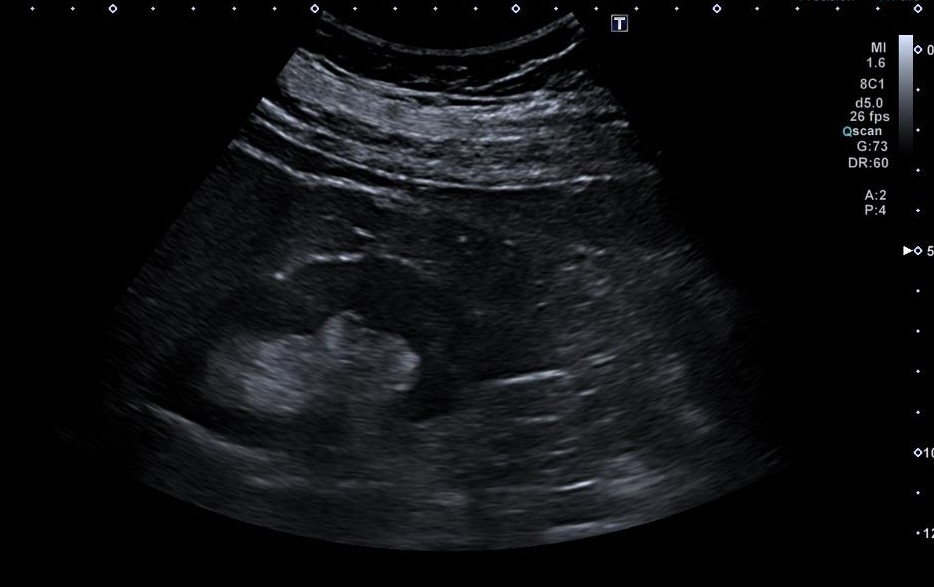

En consulta presenta dolor lumbar sin fiebre ni compromiso general. Se practica ecografía renovesical en la consulta, que muestra microlitiasis sin clara dilatación del sistema excretor, y una imagen anecoica bien delimitada y bilobulada, suprapúbica, en plano superior a vejiga de 1300 cc, Se realiza analítica urgente, objetivándose fracaso renal agudo, FRA, (FG 25 ml/min, Cr 2,06 mg/dl). Dado el FRA y hallazgo ecográfico se realiza derivación urgente a Nefrología.

En Urgencias, la ecografía muestra ligera dilatación pielocalicial derecha y presencia de imagen quística. El TC con contraste evidencia litiasis obstructiva distal de 7 mm con discreta dilatación ureteropiélica y una gran masa quística bilobulada dependiente de anexo derecho (150×124×134 mm), sin descartar componente sólido.

Es valorada por ginecología donde se orienta como posible pseudoquiste peritoneal, sin descartar origen anexial por no visualizarse el ovario derecho.